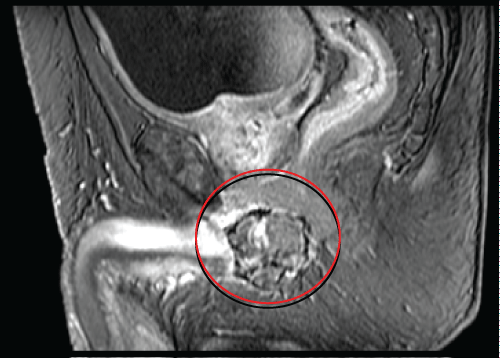

We present the case of a 71-years-old Caucasian male, with a past medical history of hypertension, Benign Prostatic Hyperplasia (BPH) and previous inguinal hernia repair. In November 2002, he underwent a laparoscopic left radical nephrectomy for a 10-cm CRCC of the left kidney with perirenal fatty tissue involvement and thrombosis of the left renal vein (pT3b N0). Patient was followed up regularly on the basis of the EAU guidelines on renal cancer. After a 14-year follow-up he presented a painless, irregular, solid mass of the perineum. MRI scan of the pelvis and perineum revealed a dishomogeneous solid expansive lesion with polylobate profiles of 52 × 58 mm, that originated from the crus of right corpus cavernosum: The mass was placed posteriorly to the base of the penis and strictly related to the internal profile of the right ischiopubic branch with partial compression and dislocation to the left of the anal canal and of the corpus spongiosum of the urethra (Figure 1a and Figure 1b). Moreover, the mass reached the limit of the membranous urethra. A trans-perineal ultrasound guided biopsy of the lesion was performed, and the pathological result showed a metastasis of CRCC. A multi-disciplinary meeting was scheduled. The patients presented favorable prognosis according to Heng and Memorial Sloan-Kettering Cancer Center (MSKCC) criteria and would have benefited from surgical resection of this single metastasis. In order to reduce surgical risk during the exeresis of the mass, the patient was treated with 4 cycles of pazopanib, as presurgical modality. Adverse effects were G1 increase in blood pression and grade 2 diarrhea symptoms. In April 2017, a follow-up-scheduled MRI scan demonstrated volumetric a 30% reduction of the perineal lesion (Figure 2a and Figure 2b). Thus, in June 2017, this patient underwent metastasectomy of the perineal mass by a median perineal access. The mass was smoothly dissected from the corpus cavernosum and the corpus spongiosum of the urethra (Figure 3a, Figure 3b and Figure 3c). The final pathological report revealed metastatic carcinoma from the right corpus cavernosum, compatible with RCC dissemination, and with negative surgical margins. According to complete resection, no TMT was proposed after surgery. At 12-month follow-up, the patient is in general good health status, and total body CT scan showed no recurrences.

Figure 1A: MRI scan revealed a solid expansive lesion from the crus of right corpus cavernosum (red arrow); the mass reached the limit of the membranous urethra. View Figure 1A

Figure 1B: MRI scan revealed a solid expansive lesion from the crus of right corpus cavernosum (red arrow); the mass was placed posteriorly to the base of the penis and strictly related to the internal profile of the right ischio-pubic branch. View Figure 1B